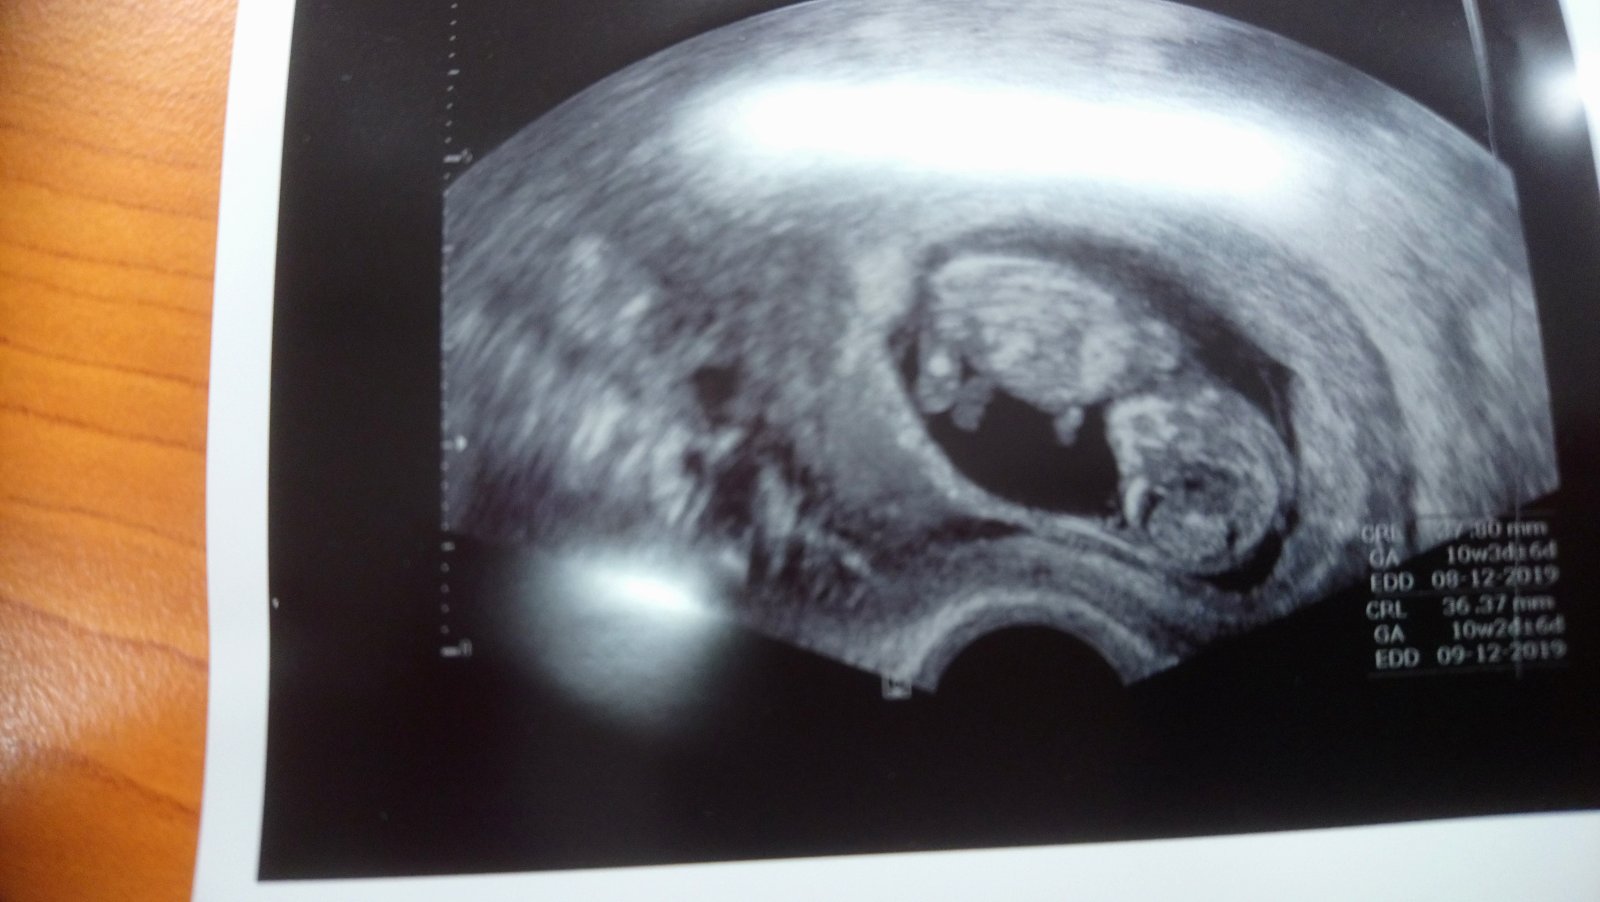

Ahoj holky! Tak druhá kontrola je úspěšně za námi má dvě ruce dvě nohy tak snad to bude dobrý 😀 Bylo super se dívat na té obrazovce jak se tam furt vrtí, málem jsem se tam rozbrečela 😅 Momentálně jsem 10+4 a genetika mě čeká za tři týdny, všem ostatním co je čeká kontrola přeji ať je vše O.K